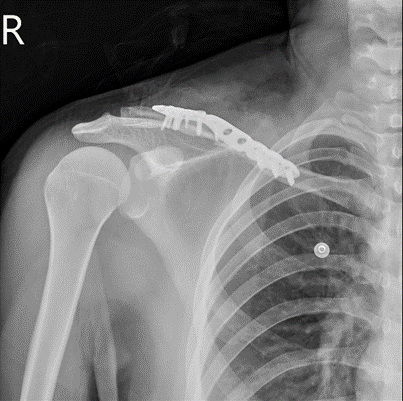

上腕骨大結節骨折 手術

またもや肩の手術 暁の星を掴み取れ

またもや肩の手術 暁の星を掴み取れ

射法 Com 射法は寝て待て 歩射 左肩骨折

肩というか上腕骨というか 暁の星を掴み取れ

左の肩と左の膝 暁の星を掴み取れ

骨折日記 今回の手術内容 新しいことを知るのって楽しい

肩というか上腕骨というか 暁の星を掴み取れ